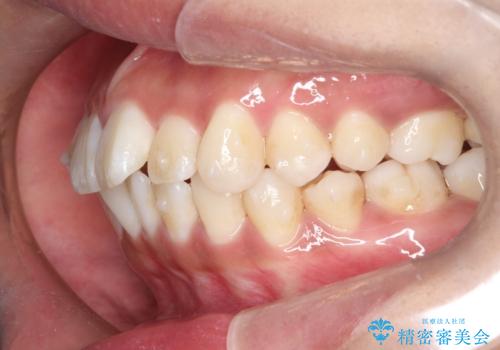

がたがたをインビザラインで整った歯並びへ

- 全体的ながたつきを主訴に来院されました。

抜歯矯正も考えられる状態でしたが、患者様が非抜歯での矯正を希望されたため、歯と歯の間をわずかに削りスペースを作り、全体を整える計画としました。